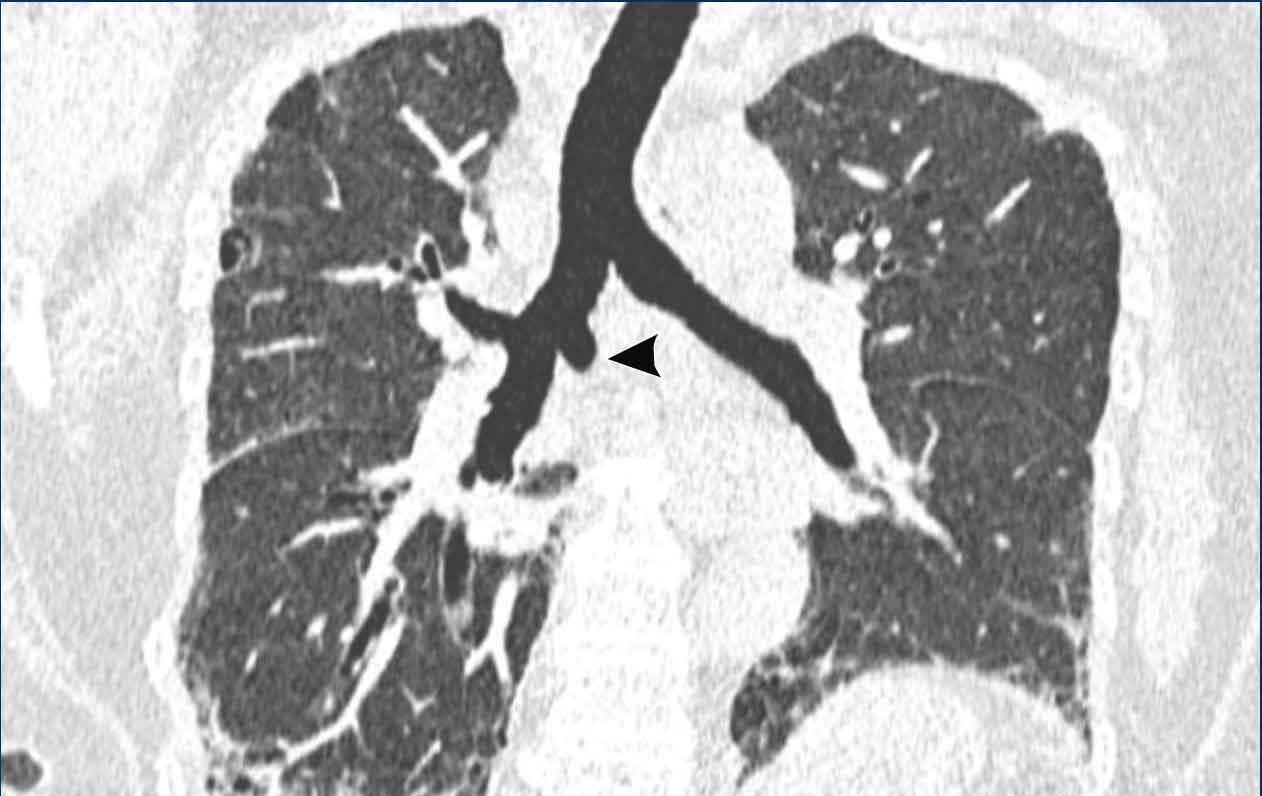

Đây là một trường hợp khác, trong đó tĩnh mạch azygos đi qua rãnh liên thùy azygos (đầu mũi tên).

Phế quản khí quản

Trong biến thể phế quản khí quản, thùy trên phổi phải được thông khí một phần bởi một phế quản xuất phát trực tiếp từ khí quản phía trên carina.

Hình ảnh

Phế quản khí quản phát hiện tình cờ ở nam giới 28 tuổi được chụp CT theo dõi ung thư (hình ảnh mặt cắt ngang), và ở nam giới 2 tuổi được chụp CT vì nhiễm trùng tái phát (hình ảnh mặt cắt vành).